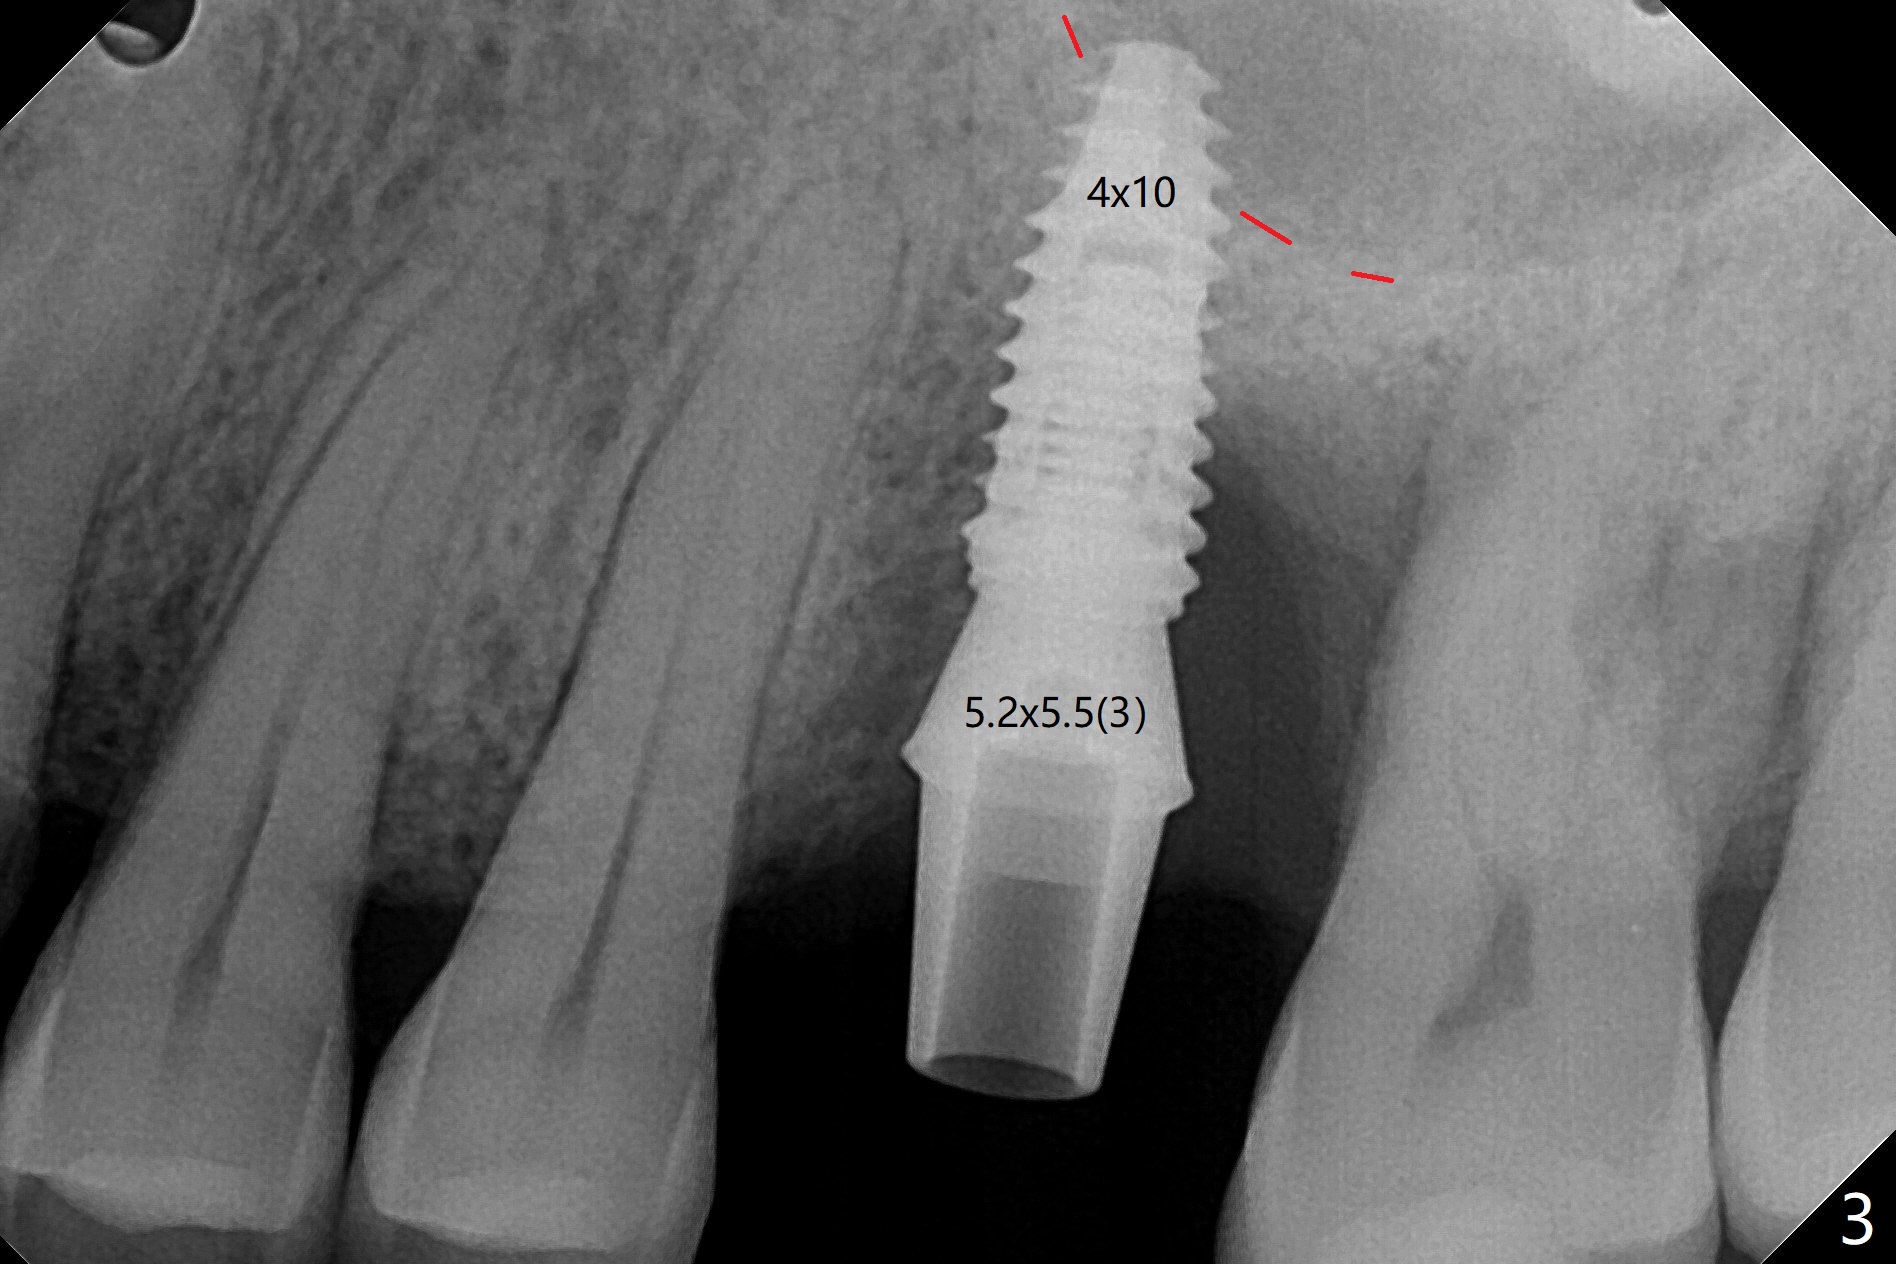

切开,使用导板完成初步钻洞,然后应用特殊上颌窦提升骨凿,顶端象环形刀,两侧有锥形刀刃(图一:箭头,防止骨凿突然进入上颌窦),由于窦底硬,骨凿并没有完全提升窦底(图二:红虚线)。使用短一号植体(图三),恰好进入上颌窦(没有骨粉),利用植体和基台固定骨粉(图四:*),覆盖两张PRF膜,将两侧厚的粘骨膜瓣尽量靠拢(图五)。最后树脂敷料。术后八天病人抱怨伤口和邻牙疼痛,骨粉被水牙线冲出来,进行邻牙咬合调整,疼痛即刻减轻(图六),再服用抗生素一周。一周后仍有轻度不适,局部牙龈正常,没有触痛。No Caries Magic Sinus Lifter 提升 Xin Wei, DDS, PhD, MS 1st edition 04/02/2021, last revision 04/18/2021